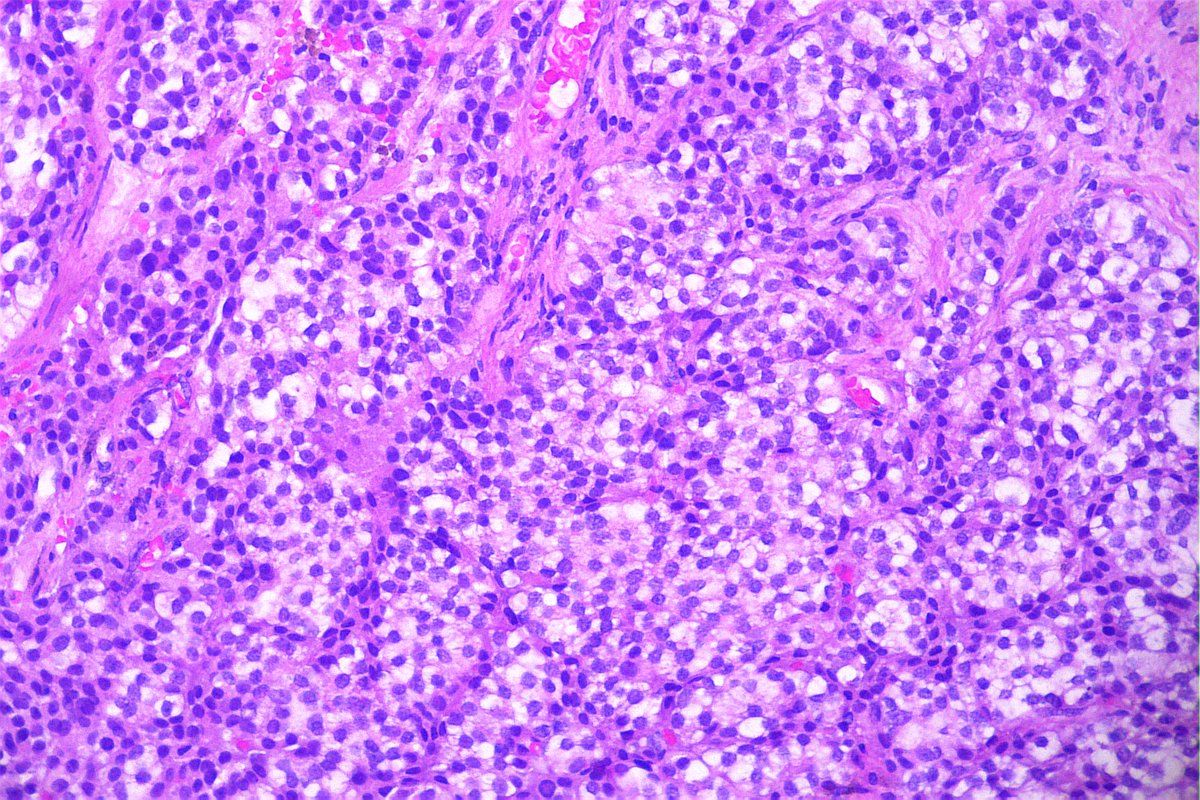

@GeronimoJrLapac

Ger么nimo Jr.

2 months

F, 47yo. The clinical information is: subepithelial lesion in the ileocecal valve. #gipath